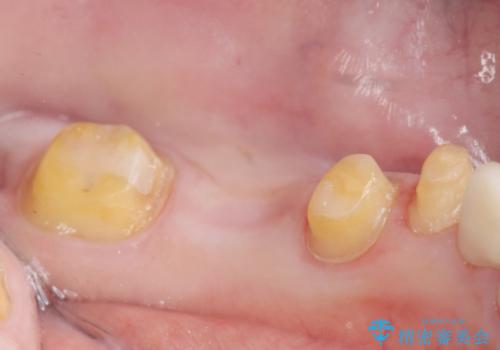

- 笑った時に大きく見えてしまう奥歯の銀歯ブリッジを白くしたいと希望され来院されました。

強度があり、審美性にも優れるジルコニアブリッジに置き替えていく治療計画としました。

- 39.6万円(ジルコニアクラウン×3・仮歯×3)費用は治療当時の料金となります

ブリッジに見えない自然な仕上がりに喜んでいただくことができました。